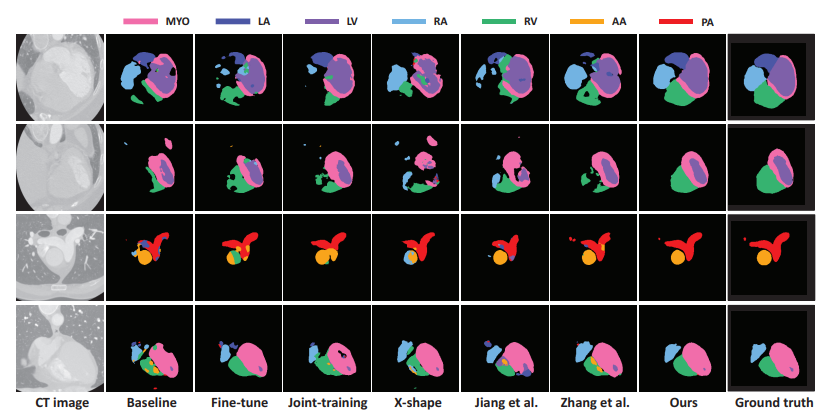

그리고 위는 정성적 결과입니다.

Ours 방식이 타 방법론들에 비해 특히 edge 등의 윤곽에 대해 훨씬 더 정확하게 예측을 수행하고 있네요.